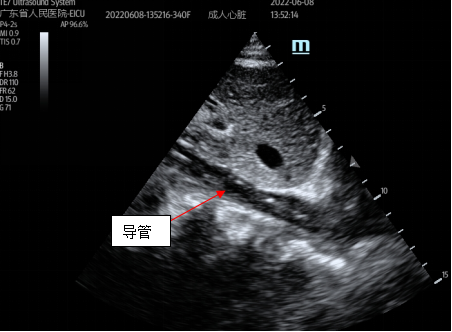

接受治疗的患者被诊断为“重症肺炎、心源性休克、ARDS、干燥综合征、肺间质病变”,由普通病房转入EICU时,已由江稳强主任带领的急诊ECMO团队行VA-ECMO支持,患者循环功能稳定后转为VV-ECMO, ARDS缓解后双肺间质性病变仍无明显改善,经院内MDT讨论后认为:患者需长期ECMO支持等待肺移植。EICU团队与体外循环团队讨论后认为:切换为单管双腔ECMO插管可有效降低院感发生率,为患者提供更舒适的救治方式,并尽早在清醒状态下进行康复治疗。经家属同意,立即为患者进行了经胸超声引导下双腔颈静脉插管,继续VV-ECMO支持治疗。

双腔插管置管成功